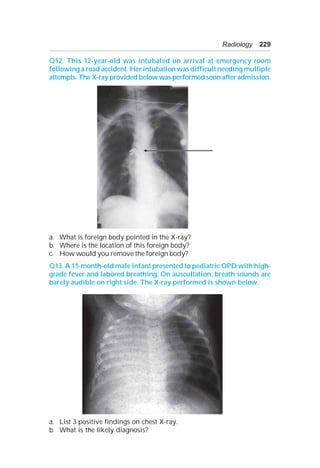

c. Endoscopy—diagnostic and therapeutic.

d. 5 abdominal thrust (Hemlich manouver) with the child sitting or lying

down.

A 12:

a. Broken tooth.

b. Right main bronchus.

c. Rigid bronchoscopy.

242 OSCE in Pediatrics

A 13: